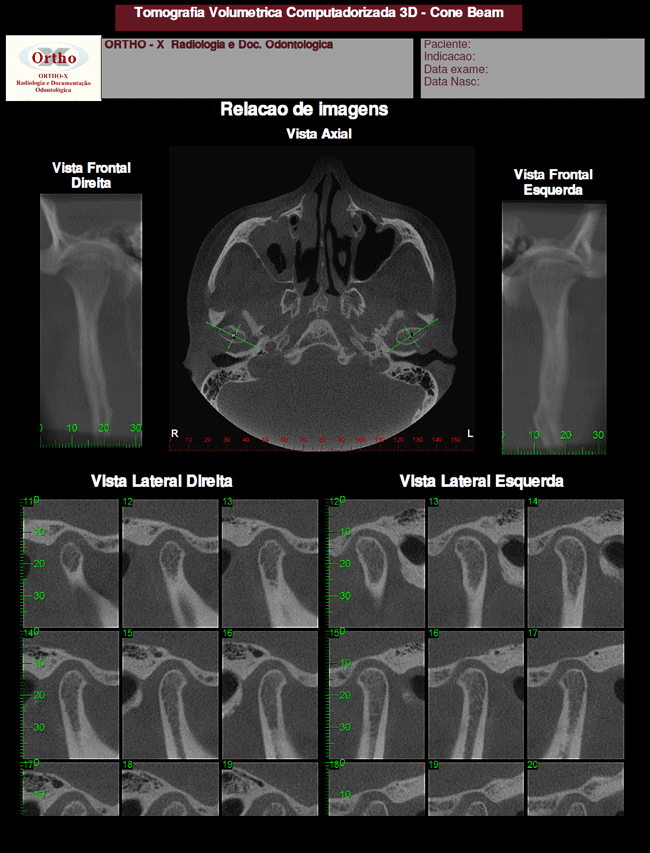

Exemplo de Exames: ATM